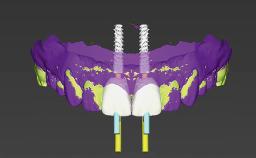

Immediate Replacement of Four Mandibular Anterior Teeth with a Conventionally Loaded Implant-Supported Fixed Dental Prosthesis

This case from German Gallucci, Adam Hamilton, and Teresa Chanting Sun details immediate placement with a conventional loading protocol (type 1C). It demonstrates a digital workflow combined with risk assessment to determine the best possible treatment approach for replacing mandibular anterior teeth.

| Number of implants | Two - Three |

| Biological | Screw-retained restorations with appropriate contours |

| Prosthetic volume | Adequate. Space available for ideal anatomy of the restoration |

| Inter-occlusal space | Adequate. Capable to create an anatomically & functionally correct planned restoration |

| Number of implants | >2 (non-splinted) or ≥ 2 (splinted) |